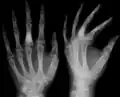

X-ray showing calcified enchondromas localized in finger a 37-year-old patient affected with Ollier disease